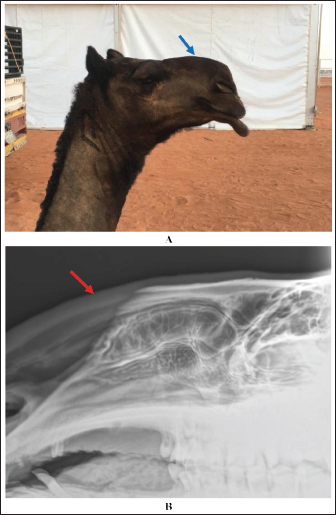

Extension and stretching of the lips in camels due to daily massage of the lips and sometimes binding with a rubber band resulted in blood congestion and lip enlargement (Fig. 7). Radiographic evaluation of filler materials in the perinasal region showed swelling of the soft tissues to the extent of variable degrees owing to the injected fillers; the injected substances appeared gray and had a soft tissue density (Fig. 8). In the injected lips, the injected filler was hypoechoic, and the scanning manner of the injected lips appeared heterogeneous (Fig. 9). In the perinasal area, the filler material appeared as either hypoechogenic or anechoic spots (Fig. 10). In infrared thermography (IRT), stretched lips appeared lighter and more heterogeneous than the darker and homogenous lips of healthy camels. In addition, the injected lip sites appeared darker than the surrounding tissue as their temperature was relatively higher when compared with healthy non-injected lip tissue (Fig. 11). Figure 12 shows a camel with enlargement of the lips due to filler injection, while Figure 13 shows enlargement of the soft palate or dulla and clitoris due to testosterone hormonal injection.

Fig. 8. Enlargement of the perinasal area in a female camel due to injection of filler material (blue arrow) (A). Image (B) shows a lateral radiographic view of the same camel, showing the gray-colored injected filler material in the perinasal region (red arrow).

Fig. 12. Extension and stretching of the lips in two female camels (A and B) following filler injection.

Radiography is also valuable for determining the injected filler materials in the perinasal region. Radiographic evaluation revealed swelling of the soft tissues to different extents owing to injected fillers; the injected substances appeared grayish with a variable soft tissue density. This finding was not correlated with those reported by Kwon et al. (2018), who found the radiopaque density of an unknown filler material in three cases, and Valiyaparambil et al. (2009) who reported a case of an unusual soft tissue radiopacity-radiographic appearance of dermal filler. The reason for the differences detected in tissue density may be due to the various types of injected fillers, whereas the most popular injected filler material in camels is hyaluronic acid (Tharwat and Al-Hawas, 2021). Our findings clearly demonstrate the usefulness of radiography as a diagnostic imaging technique for the precise detection of injected cosmetic fillers in the perinasal area and as a tool for detecting their expansion in the soft tissues. These findings agree well with recently reported findings in humans (Kroumpouzos et al., 2023) and camels (Tharwat et al., 2024b). The use of radiography in this study has some disadvantages. These drawbacks include not using the X-ray machine near the camels, as radiography can only be used in closed, protected rooms lined with lead. Therefore, it was necessary to move the suspected camel to safe places where the X-ray machine could be used, which would consequently waste time.